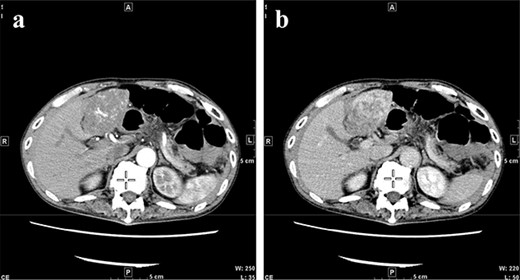

A 77-year-old man was referred to the Department of Gastroenterology at our hospital for suspicion of hepatocellular carcinoma and cancerous peritonitis. He was scheduled to be hospitalized for a thorough examination at a later date. However, 3 days after his first visit, he returned to the Emergency Department with a complaint of abdominal distension. He was hospitalized on the same day with a diagnosis of intra-abdominal bleeding due to a ruptured tumor in the lateral section of the liver. Computed tomography (CT) and magnetic resonance imaging (MRI) revealed a tumor with a maximum diameter of 8 cm in the lateral hepatic region and ascites around the liver and in the pelvic floor. Dynamic CT showed blood vessel-like early staining inside the tumor, and the contrast effect gradually enhanced (Fig. 1). During gadolinium ethoxybenzyl diethylenetriamine pentaacetic acid-enhanced MRI, this contrast effect gradually increased from the peripheral part toward the hepatocyte phase from the arterial phase (Fig. 2). Levels of tumor markers (alpha-fetoprotein, protein induced by vitamin K absence or antagonist-II, carcinoembryonic antigen and carbohydrate antigen 19–9) were within the normal range (Table 1). Based on the imaging findings, a diagnosis of spontaneously ruptured hepatic hemangioma was made. Since the patient’s general condition was stable and there were no findings suggestive of active bleeding, he decided to undergo elective surgery. Thus, he was not requested to continue being hospitalized and was discharged. Six days after discharge, he was transported to the emergency room in a state of shock and was hospitalized the same day. With the diagnosis of hemorrhagic shock due to re-rupture of the liver tumor (Fig. 3), emergency transarterial embolization (TAE) was performed. No apparent extravasation was observed on angiography, and A3 was embolized. Seven days later, he underwent left lateral hepatic segmentectomy. The postoperative course was generally good. The post-ruptured tumor was found in the left lateral segment, the cut surface was white, the edges were brown and the boundaries were unclear (Fig. 4). Histopathological examination revealed that sections of the white and brown parts of the margin were viable tumors, showing highly atypical spindle-shaped cells, arranged like sinusoidal vessels and partly solid, and there were many mitotic figures. There was no capsule, and the tumor infiltrated the surrounding liver parenchyma (Fig. 5a–c). Immunostaining showed CD31 (+), CD34 (partially positive), CK-CAM5.2 (−), α-SMA (−), HMB45 (indeterminate) and p53 (+), and the patient was diagnosed with hepatic angiosarcoma (Fig. 5d). Fever was observed 21 days after surgery, and CT was performed, revealing multiple masses in the liver (Fig. 6a). Another CT scan was performed 27 days postoperatively, which suggested that the liver masses were rapidly increasing; hepatic angiosarcoma recurrence was then confirmed (Fig. 6b). The patient requested the best supportive care at home and was discharged 31 days after the operation. He died at home 36 days after surgery.

CT at initial admission points out a tumor with a maximum diameter of 8 cm in the lateral hepatic region and ascites around the liver. Dynamic CT shows blood vessel-like early staining inside the tumor, and the contrast effect gradually enhances. (a) Arterial phase, (b) equilibrium phase. CT, computed tomography.